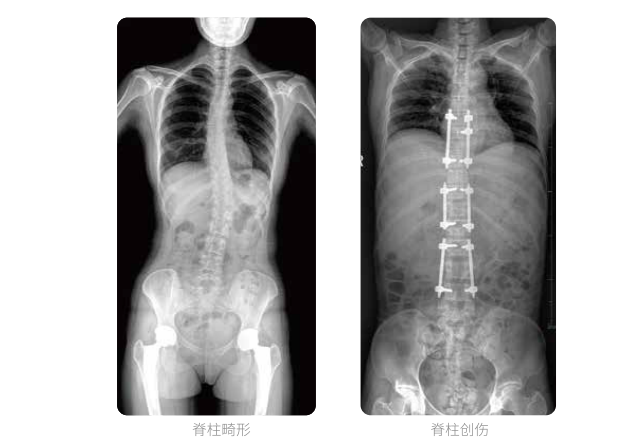

大視野不拼接 一次曝光覆蓋全脊柱

全脊柱臨床影像

PLX8600大視野平板動態(tài)DR全脊柱一次成像攝片適用于兒童、成人、老年人腰椎退行性病變、強直性脊柱炎、脊柱結(jié)核等臨床應(yīng)用,在此類大視野的臨床拍攝中發(fā)揮了極大的價值。

PLX8600大視野平板動態(tài)DR可在透視情況下多角度觀察病灶部位,做術(shù)前診斷及術(shù)后愈合的檢查,如脊柱斜位透視,可觀察椎弓根峽部,診斷椎體是否滑脫等情況;可在脊柱運動狀態(tài)下通過透視模式觀察全脊柱狀態(tài),了解病變處脊柱的活動度及骨結(jié)構(gòu)的關(guān)系,配合點片功能快速獲得高清的關(guān)鍵幀影像,輔助醫(yī)生制定更準(zhǔn)確的手術(shù)方案。